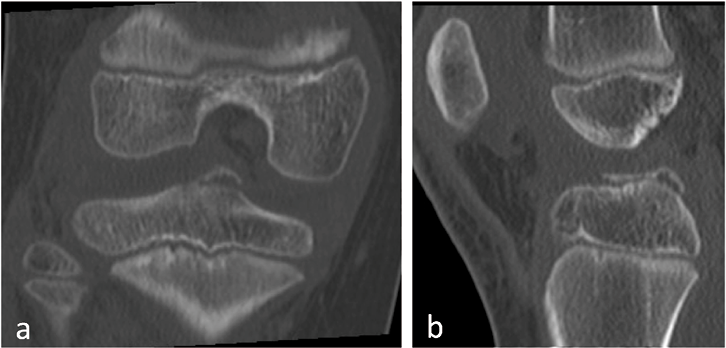

Der osteochondrale Eminentia-intercondylaris-Ausriss mit dem tibialen Ansatz des vorderen Kreuzbandes liegt intraartikulär, epiphysär und betrifft nicht die Epiphysenfuge selbst. Er zählt zu den häufigsten epiphysären Frakturen der proximalen Tibia. Diagnostiziert wird ein Eminentia-intercondylaris-Ausriss mittels Röntgendiagnostik in zwei Ebenen, wobei man das Hochstehen des osteochondralen Fragmentes beurteilen kann (Abb. 1). Während der undislozierte Meyers und McKeever Typ I konservativ in Streckstellung für 6 Wochen behandelt werden kann, müssen die dislozierten Ausrissverletzungen (Typ 2–4) arthroskopisch oder minimal-offen reponiert und mittels Schraube, Ausziehnaht oder Draht refixiert und mittels Orthese nachbehandelt werden [2]. Das Therapieziel besteht in einer Wiederherstellung der Bandstabilität, sowie der Vermeidung von Meniskus- oder Knorpelläsionen als Spätschäden [3]. Eine Sportfähigkeit besteht bei freier Funktion und symmetrischen Muskelverhältnissen nach etwa 12 Wochen [4]. Bis zum Wachstumsabschluss sollten Nachkontrollen der Kniebandstabilität durchgeführt werden, um eine dauerhafte Bandinstabilität oder eine sekundäre VKB- Insuffizienz im Langzeitverlauf auszuschließen.

Abb. 1: 8-jähriges Mädchen, Z.n. Auto gegen Fahrrad, CT des rechten Kniegelenks mit einem Eminentia intercondylaris-Ausriss, Meyers und McKeever Typ 2, a) ap, b) seitlich